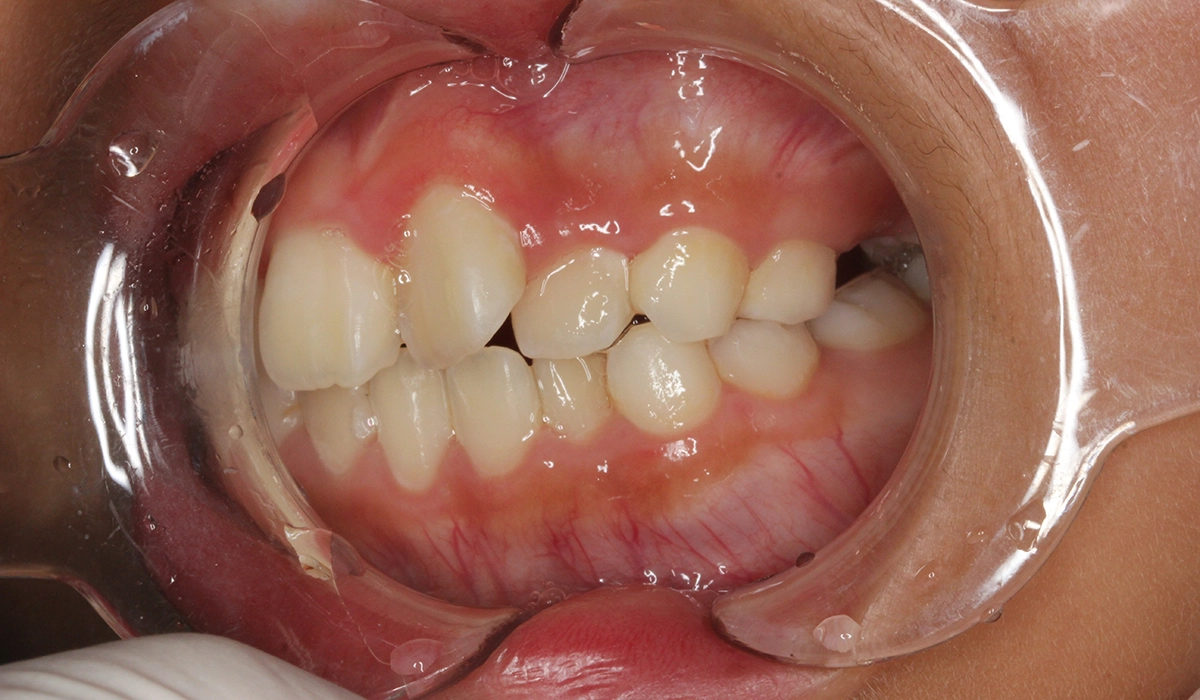

術前:右側

術後:右側